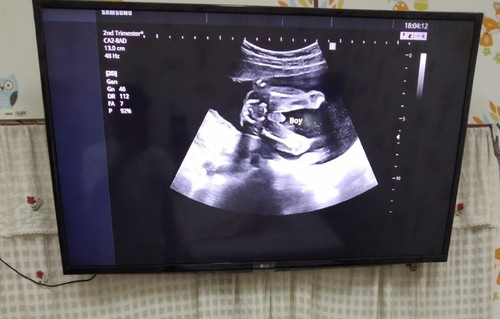

รบกวนคุณแม่ๆช่วยดูหน่อยน่ะคับ?? แบบนี้ผู้หญิงหรือผู้ชายคับ คุณหมอเขียนว่าboy ตอนนี้อายุครรภ์ภรรยาผม 20 สัปดาห์คับ

ผู้ชายค่ะ ชัดมากค่ะ

ผช นะคะ

ขอบคุณคับ แบบนี้ชัดเลยใช่ไหมคับ☺☺